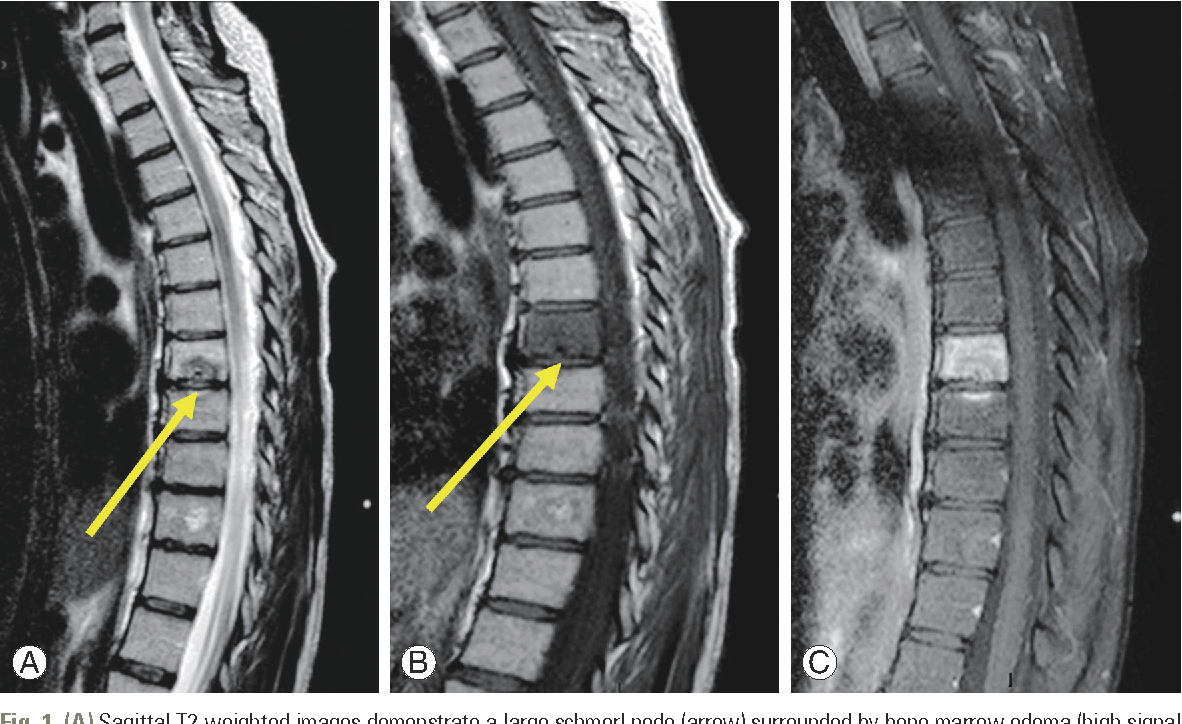

- RMN (Rezonanță Magnetică Nucleară): Oferă imagini detaliate ale țesuturilor moi, inclusiv discuri și nervi și poate arăta o eventuala extindere a herniei de disc

- Tomografie Computerizată (CT): Furnizează imagini detaliate ale oaselor pentru o mai bună vizualizare a herniei în corpul vertebral